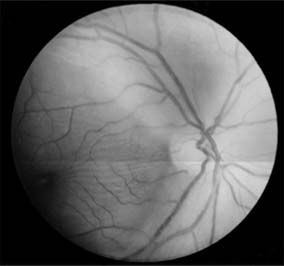

For papilledema to occur, the subarachnoid spaces around the optic nerve must be patent and connect the retrolaminar optic nerve through the bony optic canal to the intracranial subarachnoid space, thus allowing increased intracranial pressure to be transmitted to the retrolaminar optic nerve. There slow and fast axonal transport is blocked, and axonal distention, particularly noticeable at the superior and inferior poles of the optic disk, occurs as the first sign of papilledema. Hyperemia of the disk, dilated surface capillary telangiectases, blurring of the peripapillary disk margin, and loss of spontaneous venous pulsations are the signs of mild papilledema. Edema around the disk can cause a decreased sensitivity to small isopters on visual field testing, but circumferential retinal folds with changes in the internal limiting membrane reflexes (Paton's lines) will eventually become evident as the retina is pushed away from the choked disk; when the retina is pushed away, the blind spot will be enlarged to large isopters on visual field testing as well. In acute papilledema, probably as a consequence either of markedly elevated or rapidly increasing intracranial pressure, there are hemorrhages and cotton-wool spots, indicating vascular and axonal decompensation with the attendant risk of acute optic nerve damage and visual field defects (Figure 14-14). There may also be peripapillary edema (which can extend to the macula) and choroidal folds. In chronic papilledema (new window  Figure 14-15), which is likely to be the consequence of prolonged moderately raised intracranial pressure, a process of compensation appears to limit the optic disk changes such that there are few if any hemorrhages or cotton-wool spots. With persistent raised intracranial pressure, the hyperemic elevated disk gradually becomes gray-white as a result of astrocytic gliosis and neural atrophy with secondary constriction of retinal blood vessels, thus leading to the stage of atrophic papilledema (Figure 14-16). There may also be retinochoroidal collaterals (previously known as opticociliary shunts) linking the central retinal vein and the peripapillary choroidal veins, which develop when the retinal venous circulation is obstructed in the prelaminar region of the optic nerve. (Other causes of retinochoroidal collaterals are central retinal vein occlusion, optic nerve sheath meningioma, optic nerve glioma, and optic nerve head drusen.) Vintage papilledema is characterized by the presence of drusen-like deposits within the swollen optic nerve head.

Figure 14-16

Figure 14-16: Atrophic papilledema in a child with a cerebellar medulloblastoma. The disk is pale and slightly elevated and has blurred margins. The white areas surrounding the macula are reflected light from the vitreoretinal interface. The inferior temporal nerve fiber bundles are partially atrophic (arrows).